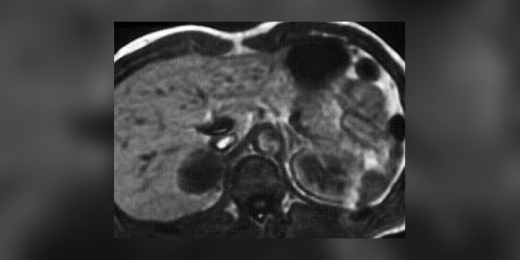

Որպես հիվանդություն ֆեոքրոմոցիտոման զարգանում է ևարտահայտվում մակերիկամների միջուկային նյութի քրոմաֆինային բջիջների հորմոնաակտիվ ուռուցքների հետևանքով։ Բարեբախտաբար հազվադեպ է հանդիպում, ախտորոշումը որոշակի դժվարություններ ունի, մանավանդ երեխաների մոտ։